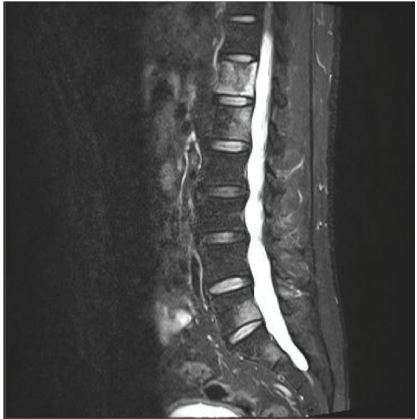

A Computed Tomography (CT) scan was ordered, which showed a 3 cm solid lesion in the left lower renal pole (Figure 1), multiple bony blasts at the dorsal, lumbar, and sacral levels, and a left adrenal lesion suggestive of metastasis (Figure 2). A brain Magnetic Resonance Imaging (MRI) was performed to complete the study and showed a right frontal lesion suggestive of metastasis.

Figure 1: CT image, a 3 cm solid lesion in the left lower renal pole.

Figure 2: MRI image, dorsal vertebral metastases.